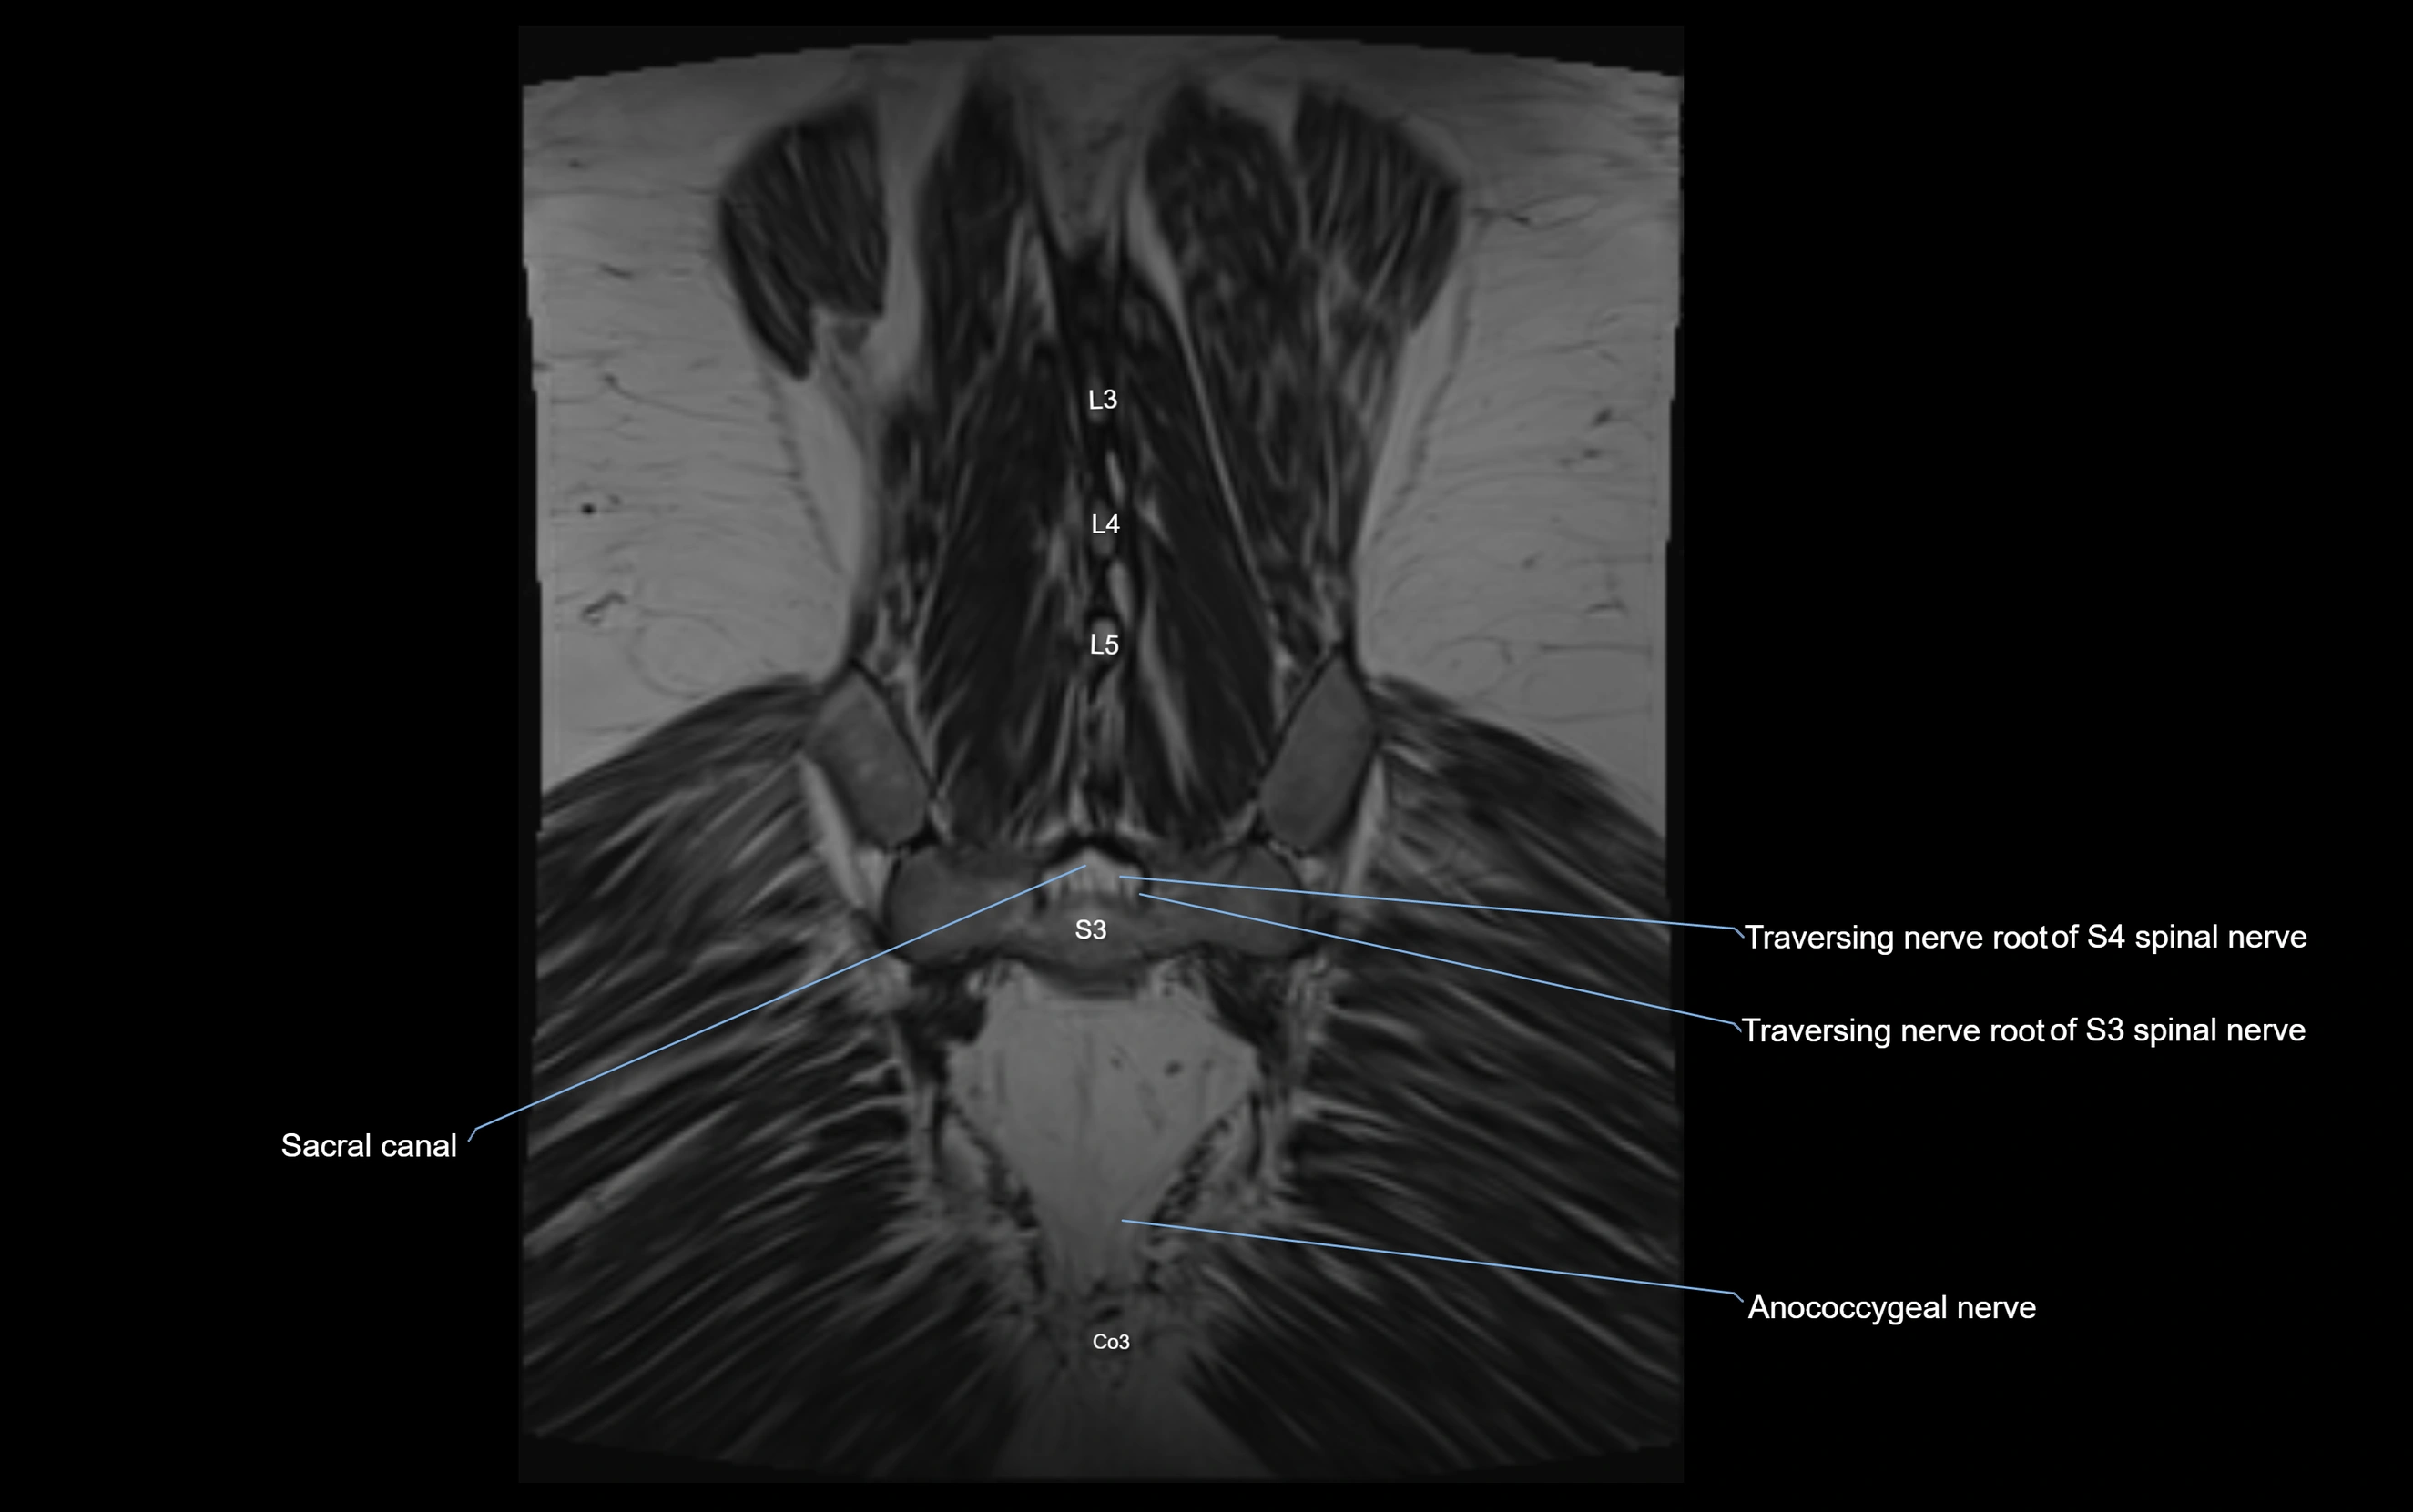

MRI image

image